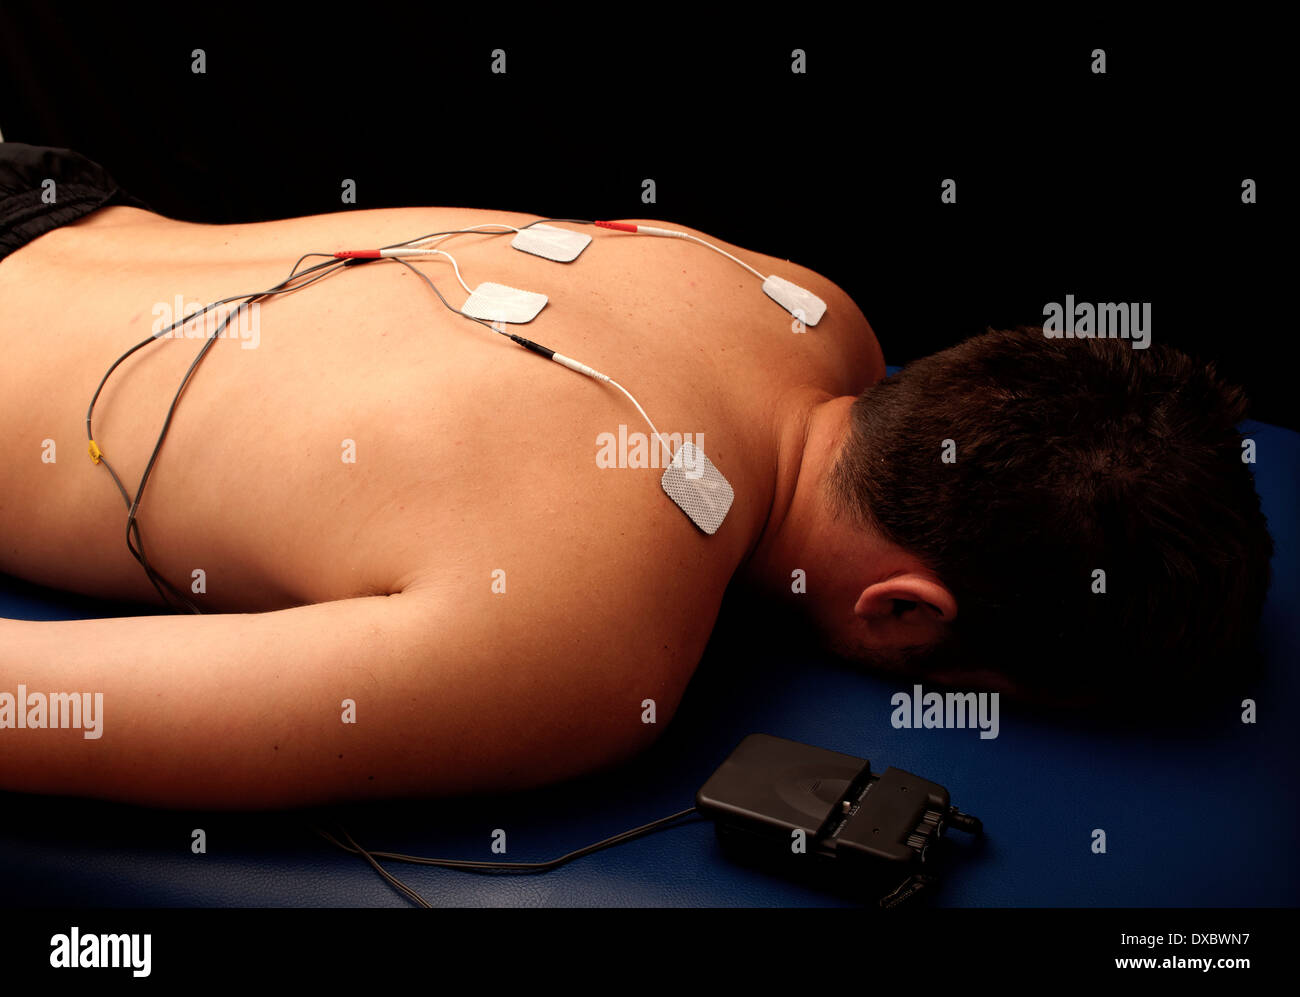

TENS Stock Photohttps://www.alamy.com/image-license-details/?v=1https://www.alamy.com/tens-image67873827.html

TENS Stock Photohttps://www.alamy.com/image-license-details/?v=1https://www.alamy.com/tens-image67873827.htmlRFDXBWN7–TENS